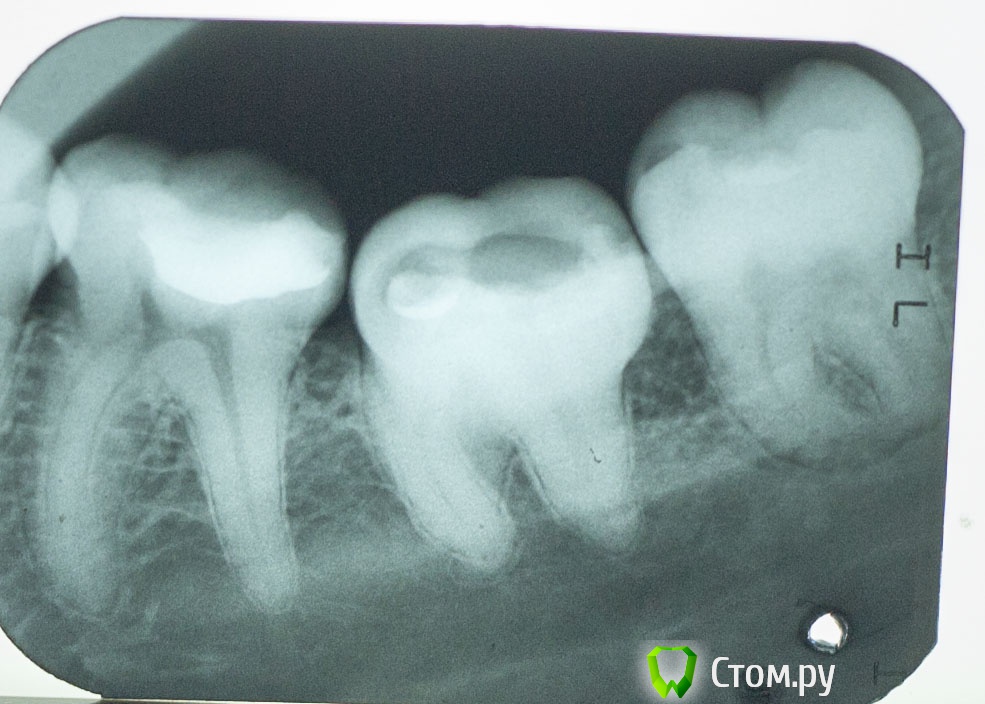

Vlad74 Опубликовано 15 января, 2014 Поделиться Опубликовано 15 января, 2014 Добрый вечер, прошу помощи. 2 месяца назад был пульпит, долго не могли определить какой зуб, ходил 2 недели в поликлинику. В итоге вроде нашли зуб 7 нижний (проводили электроодонтодиагностику показания 60, вроде бы немного болел при накусывании и постукивании), заложили мышьяк. Через 3 дня достали. Легче не стало. Через неделю болела вся левая половина верхней и нижней челюсти, наконец определили пульпитный зуб ( 5 сверху), в течении неск дней полностью запломбировали, 5 сейчас не беспокоит. Вопрос по 7 зубу. Снимок до лечения №1. Лечил в платном кабинете. Прочистили, запломбировали 1 канал, сказали остальные 2 непроходимы, поставили какую то пасту, неделю ходил с временной пломбой, боли не было. Далее поставили постоянную. После этого заболел зуб, сильная пульсация. Сделал снимок (№2), был в шоке как сделали. Через неделю обратился по гарантии. Вскрыли, заново прочистили 2 канала, поставили лекарство на неделю. Боли не было. Далее запломбировали 2 канала - 1 штифтами, 1 пастой. Сказали есть перфорации в коронковой части, заделали цементом. 3 канал не нашли, долго искали! Направили к другому врачу этой же клиники, по снимку определила ПЕРЕЛОМ корня зуба и однозначное удаление. Сейчас зуб под временной пломбой, часто напоминает о себе, реагирует на постукивание, при накусывании, немного на холод. Обратился еще к 2 стоматологам в другие клиники за советом, 1 сказал что перелома нет и нужно искать канал, 2 что каналы непроходимы и удаление. Текущий снимок №3. Пожалуйста, посоветуйте стоит ли пытаться продолжать лечение и что делать, если не найдут канал? ЗЫ Зуб значительно наклонен в сторону языка, боковая стенка зуба располагается примерно посредине жевательной поверхности соседних зубов. Спасибо Ссылка на комментарий

Vlad74 Опубликовано 15 января, 2014 Автор Поделиться Опубликовано 15 января, 2014 Спасибо. Видно ли на последнем снимке перелом корня справа? Ссылка на комментарий

Vlad74 Опубликовано 16 января, 2014 Автор Поделиться Опубликовано 16 января, 2014 Обратился к другому врачу. Сделали снимок, на снимке под другим углом не видно трещины, вроде бы это цемент на перфорации. Сказали, что выведен пломбировочный материал, вроде бы штифт, что с ним делать? На счет третьего канала сказали что скорее всего не удастся пройти, и тогда "пропитают" канал. Ссылка на комментарий